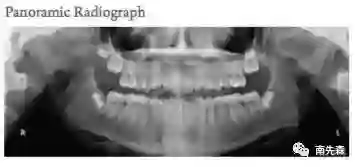

还有头颅侧位照,以便于头影测量分析,研究面部硬软组织容貌相关解剖标志点的角度关系等。

接着来看术中的图,比如头颅正位照